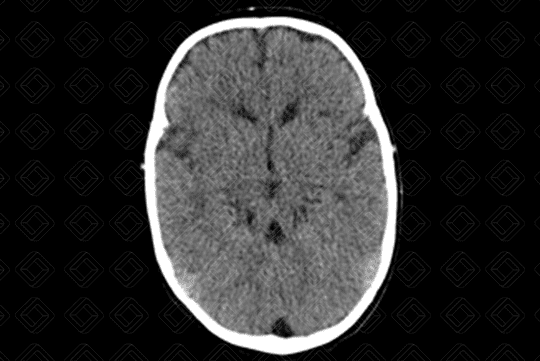

Descrição da lesão: Imagem de tomografia computadorizada do crânio evidenciando a presença de pedúnculos cerebelares superiores espessados e hipoplasia do vérmis, o que leva ao clássico sinal do "dente molar" no corte axial (asterisco).

Síndrome de Joubert: Também conhecida como malformação do dente molar, trata-se de anomalia autossômica recessiva caracterizada por hipoplasia do vérmis cerebelar e proeminência dos pedúnculos cerebelares superiores.

• Tomografia computadorizada do crânio: O bservamos o verme cerebelar fendido e o 4º ventrículo apresenta configuração em "asa de morcego";

• Ressonância magnética do crânio: F enda vermiana, aparência do "dente molar". Pedúnculos cerebelares superiores paralelos, proeminentes e no mesmo plano (raízes molares). Em alguns casos, pode cursar com mielinização anormal.